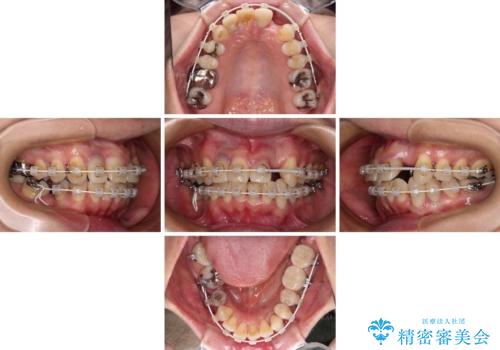

- 矯正装置

- 審美装置

- 治療期間

- 3年

- 治療回数

- 30回以上